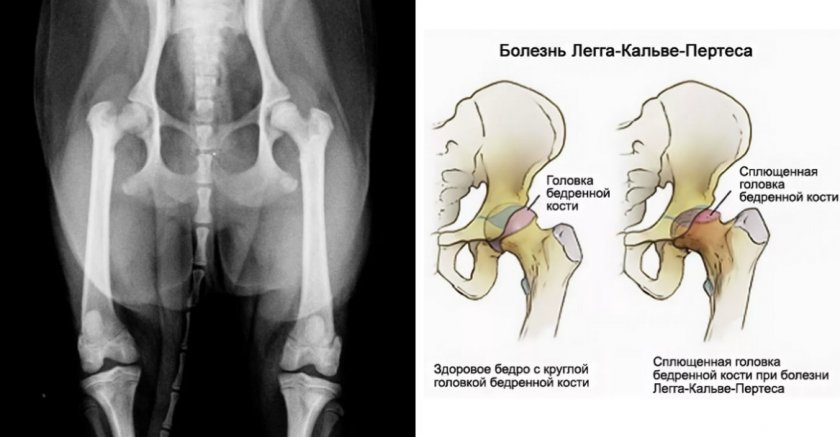

Различные патологии опорно-двигательного аппарата у собак возникают довольно часто, причём далеко не всегда их причиной являются травмы. К сожалению, домашние питомцы, как и люди, подвержены хроническим заболеваниям костей и суставов, протекающих порой очень болезненно и причиняющих множество неудобств как самому животному, так и его владельцу. Одной из таких проблем является асептический (аваскулярный) некроз головки бедренной кости, известный также под названием болезнь Легга-Кальве-Пертеса, о котором и пойдёт речь ниже.

У собаки, как и у человека, патология сначала затрагивает трубчатую кость, входящую в вертлужную впадину и являющуюся частью тазобедренного сустава. В начальной стадии развития заболевания разрушаются (некротируют) костные клетки головки и шейки кости бедра, после чего дегенеративные изменения постепенно распространяются на весь сустав, нарушая правильное сочленение его частей.

В зависимости от степени деформации головки бедра и локализации очага некроза на рентгеновском снимке заболевание может быть выражено очевидным изменением формы и внешнего вида сустава (грибовидные или седловидные изгибы, укороченная шейка, завышение большого вертела) либо быть почти незаметным, и в этом случае очень важно, чтобы рентгенограмму изучил опытный специалист.